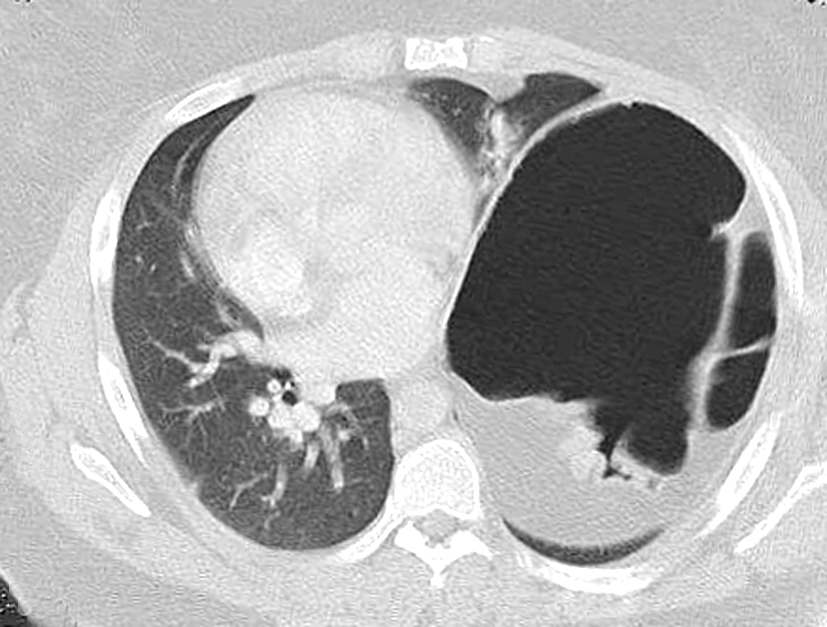

CASE 264 CT LEFT DIAPHRAGMATIC EVENTRATION YouTube What Is Diaphragmatic Eventration Diaphragmatic eventration is the abnormal elevation of a portion or entire hemidiaphragm due to a lack of muscle or nerve function while maintaining anatomical. Diaphragmatic plication is indicated for symptomatic patients and leads to significant improvement in symptoms. Clinically, diaphragmatic eventration can be impossible to differentiate from acquired paralysis. Diaphragmatic eventration is a thinning of a portion or all of. What Is Diaphragmatic Eventration.